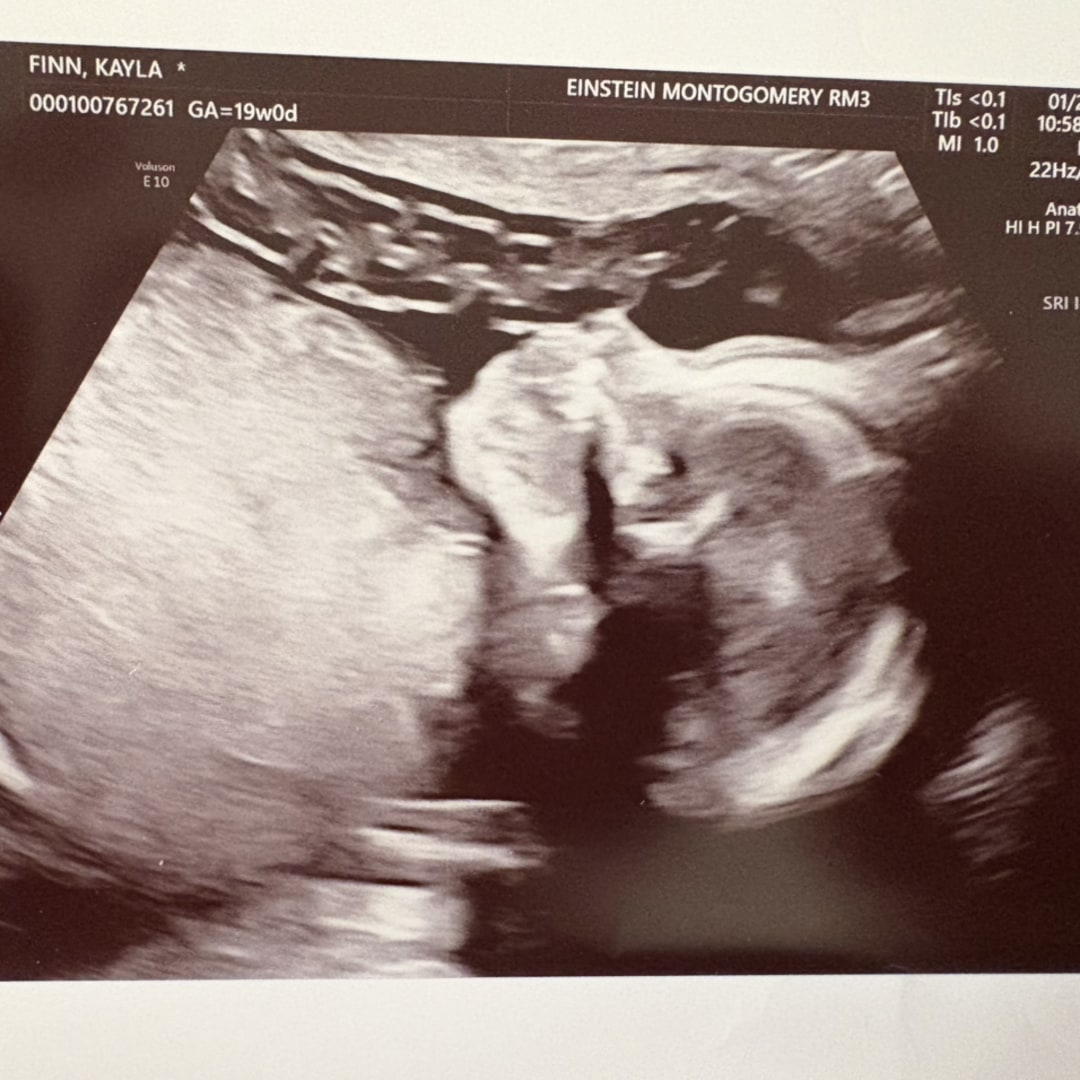

Our sweet little soccer player

Kayla & Mike Finn

Collegeville, PA

June 1, 2026